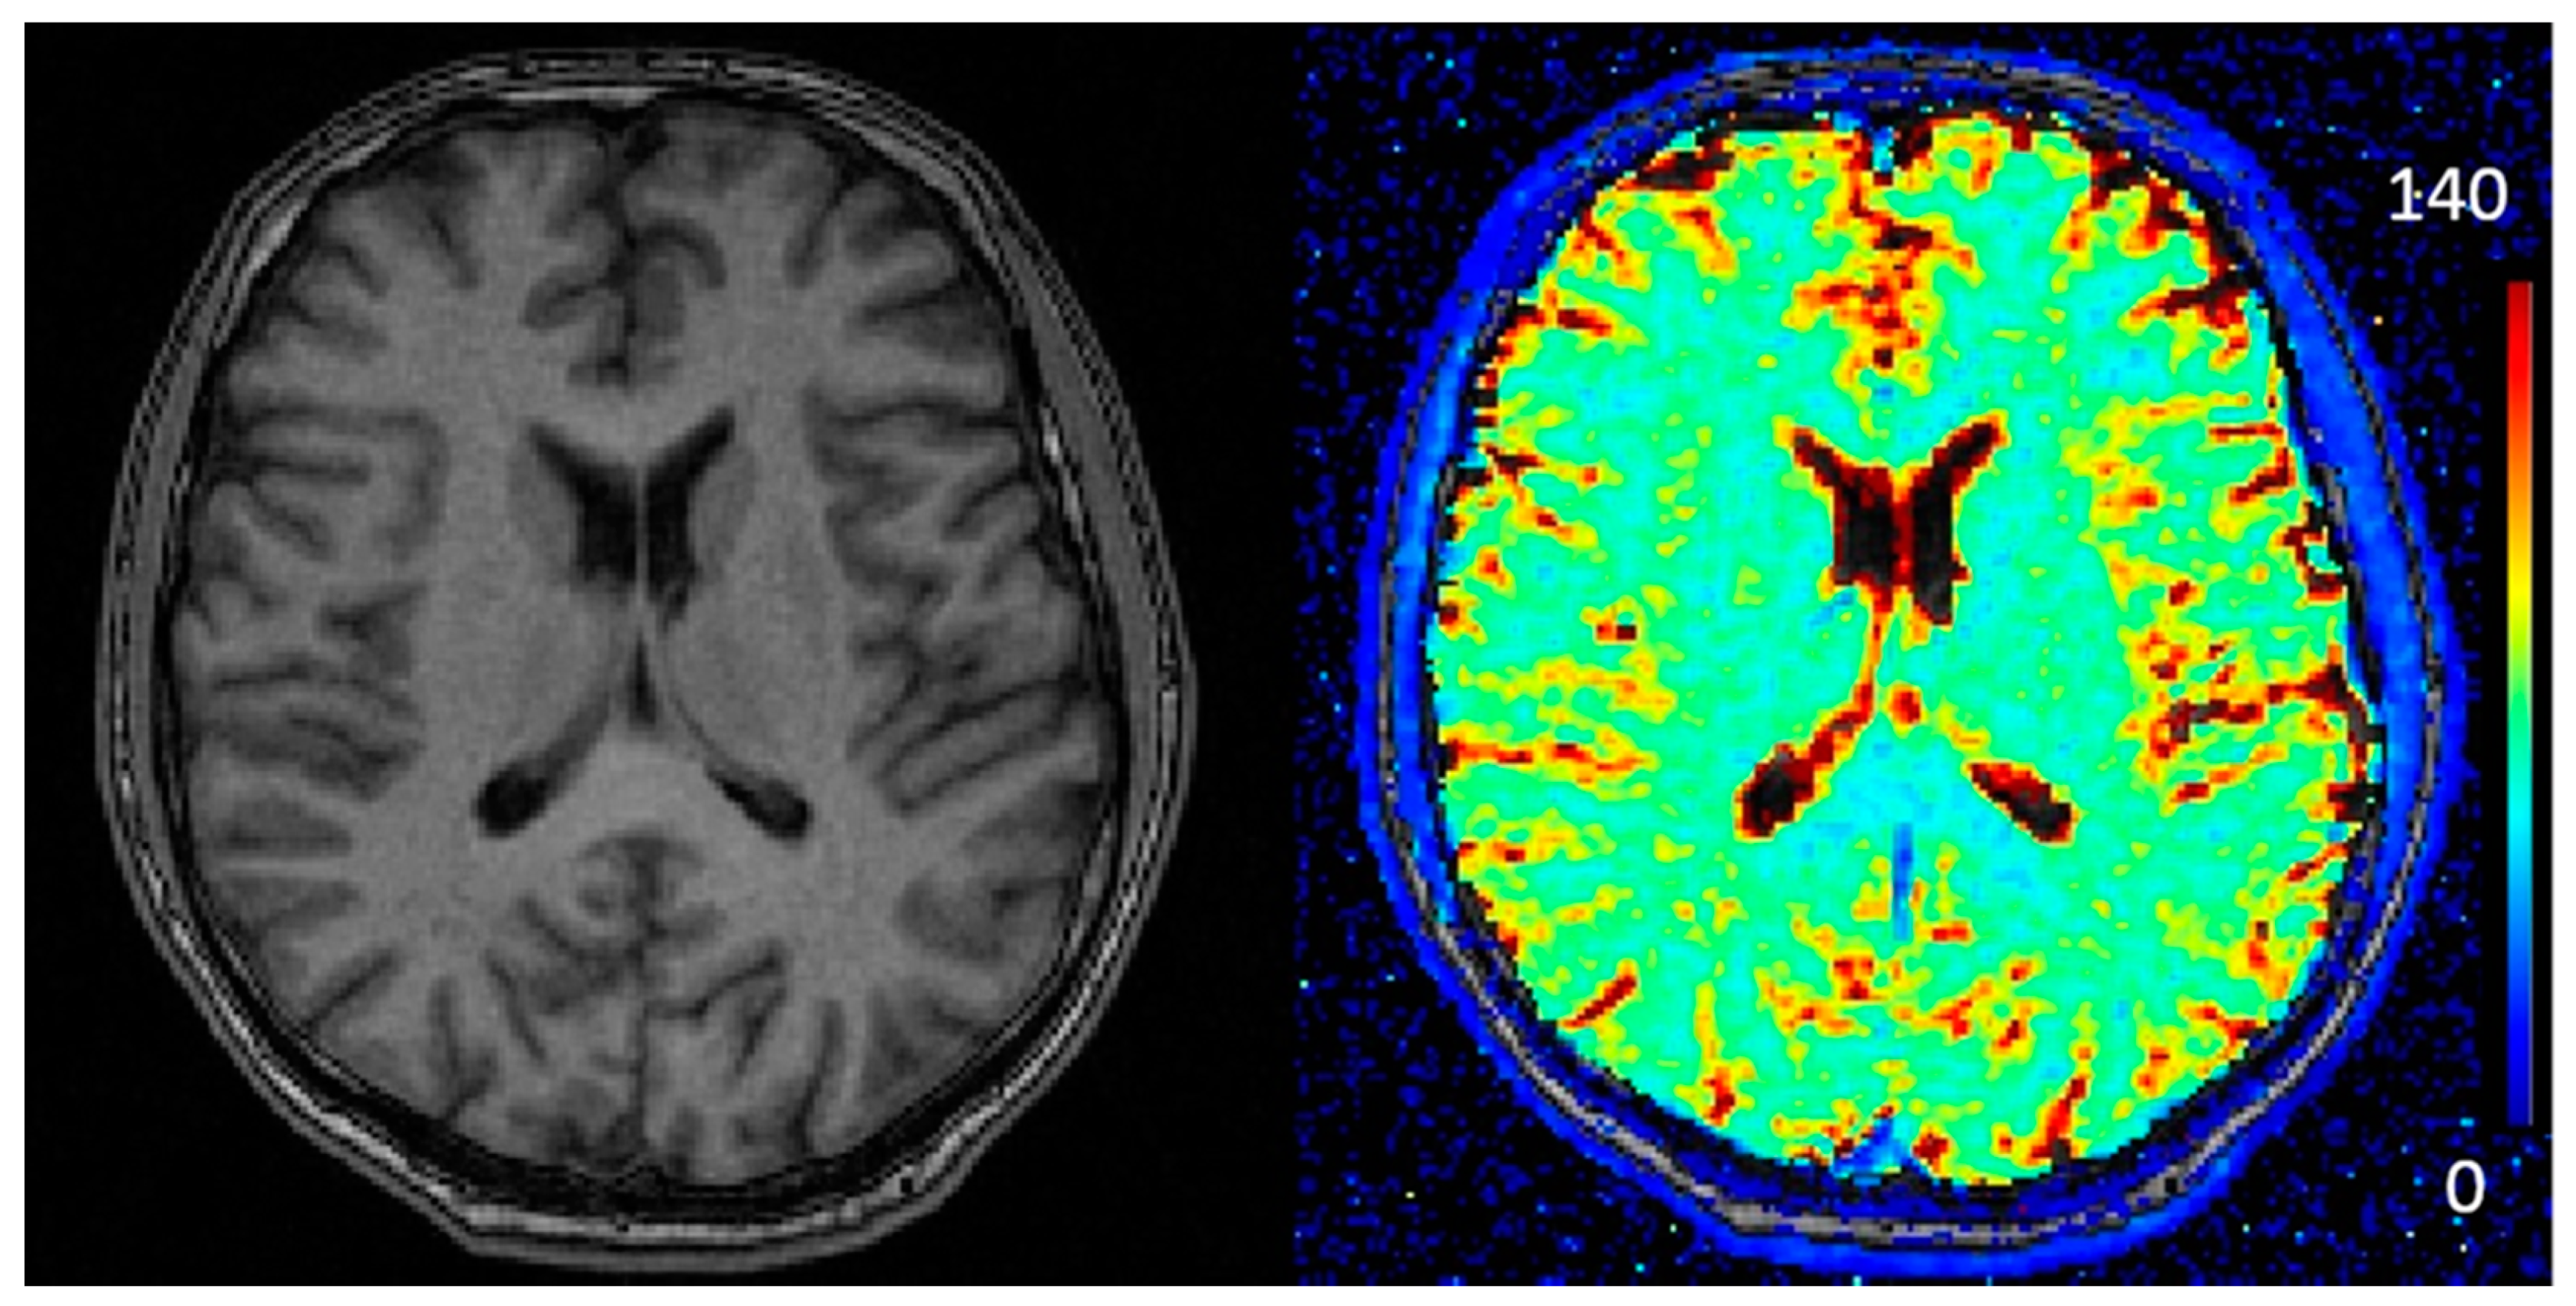

2.5. Relaxometry

2.10. Quantitative T2* Analysis